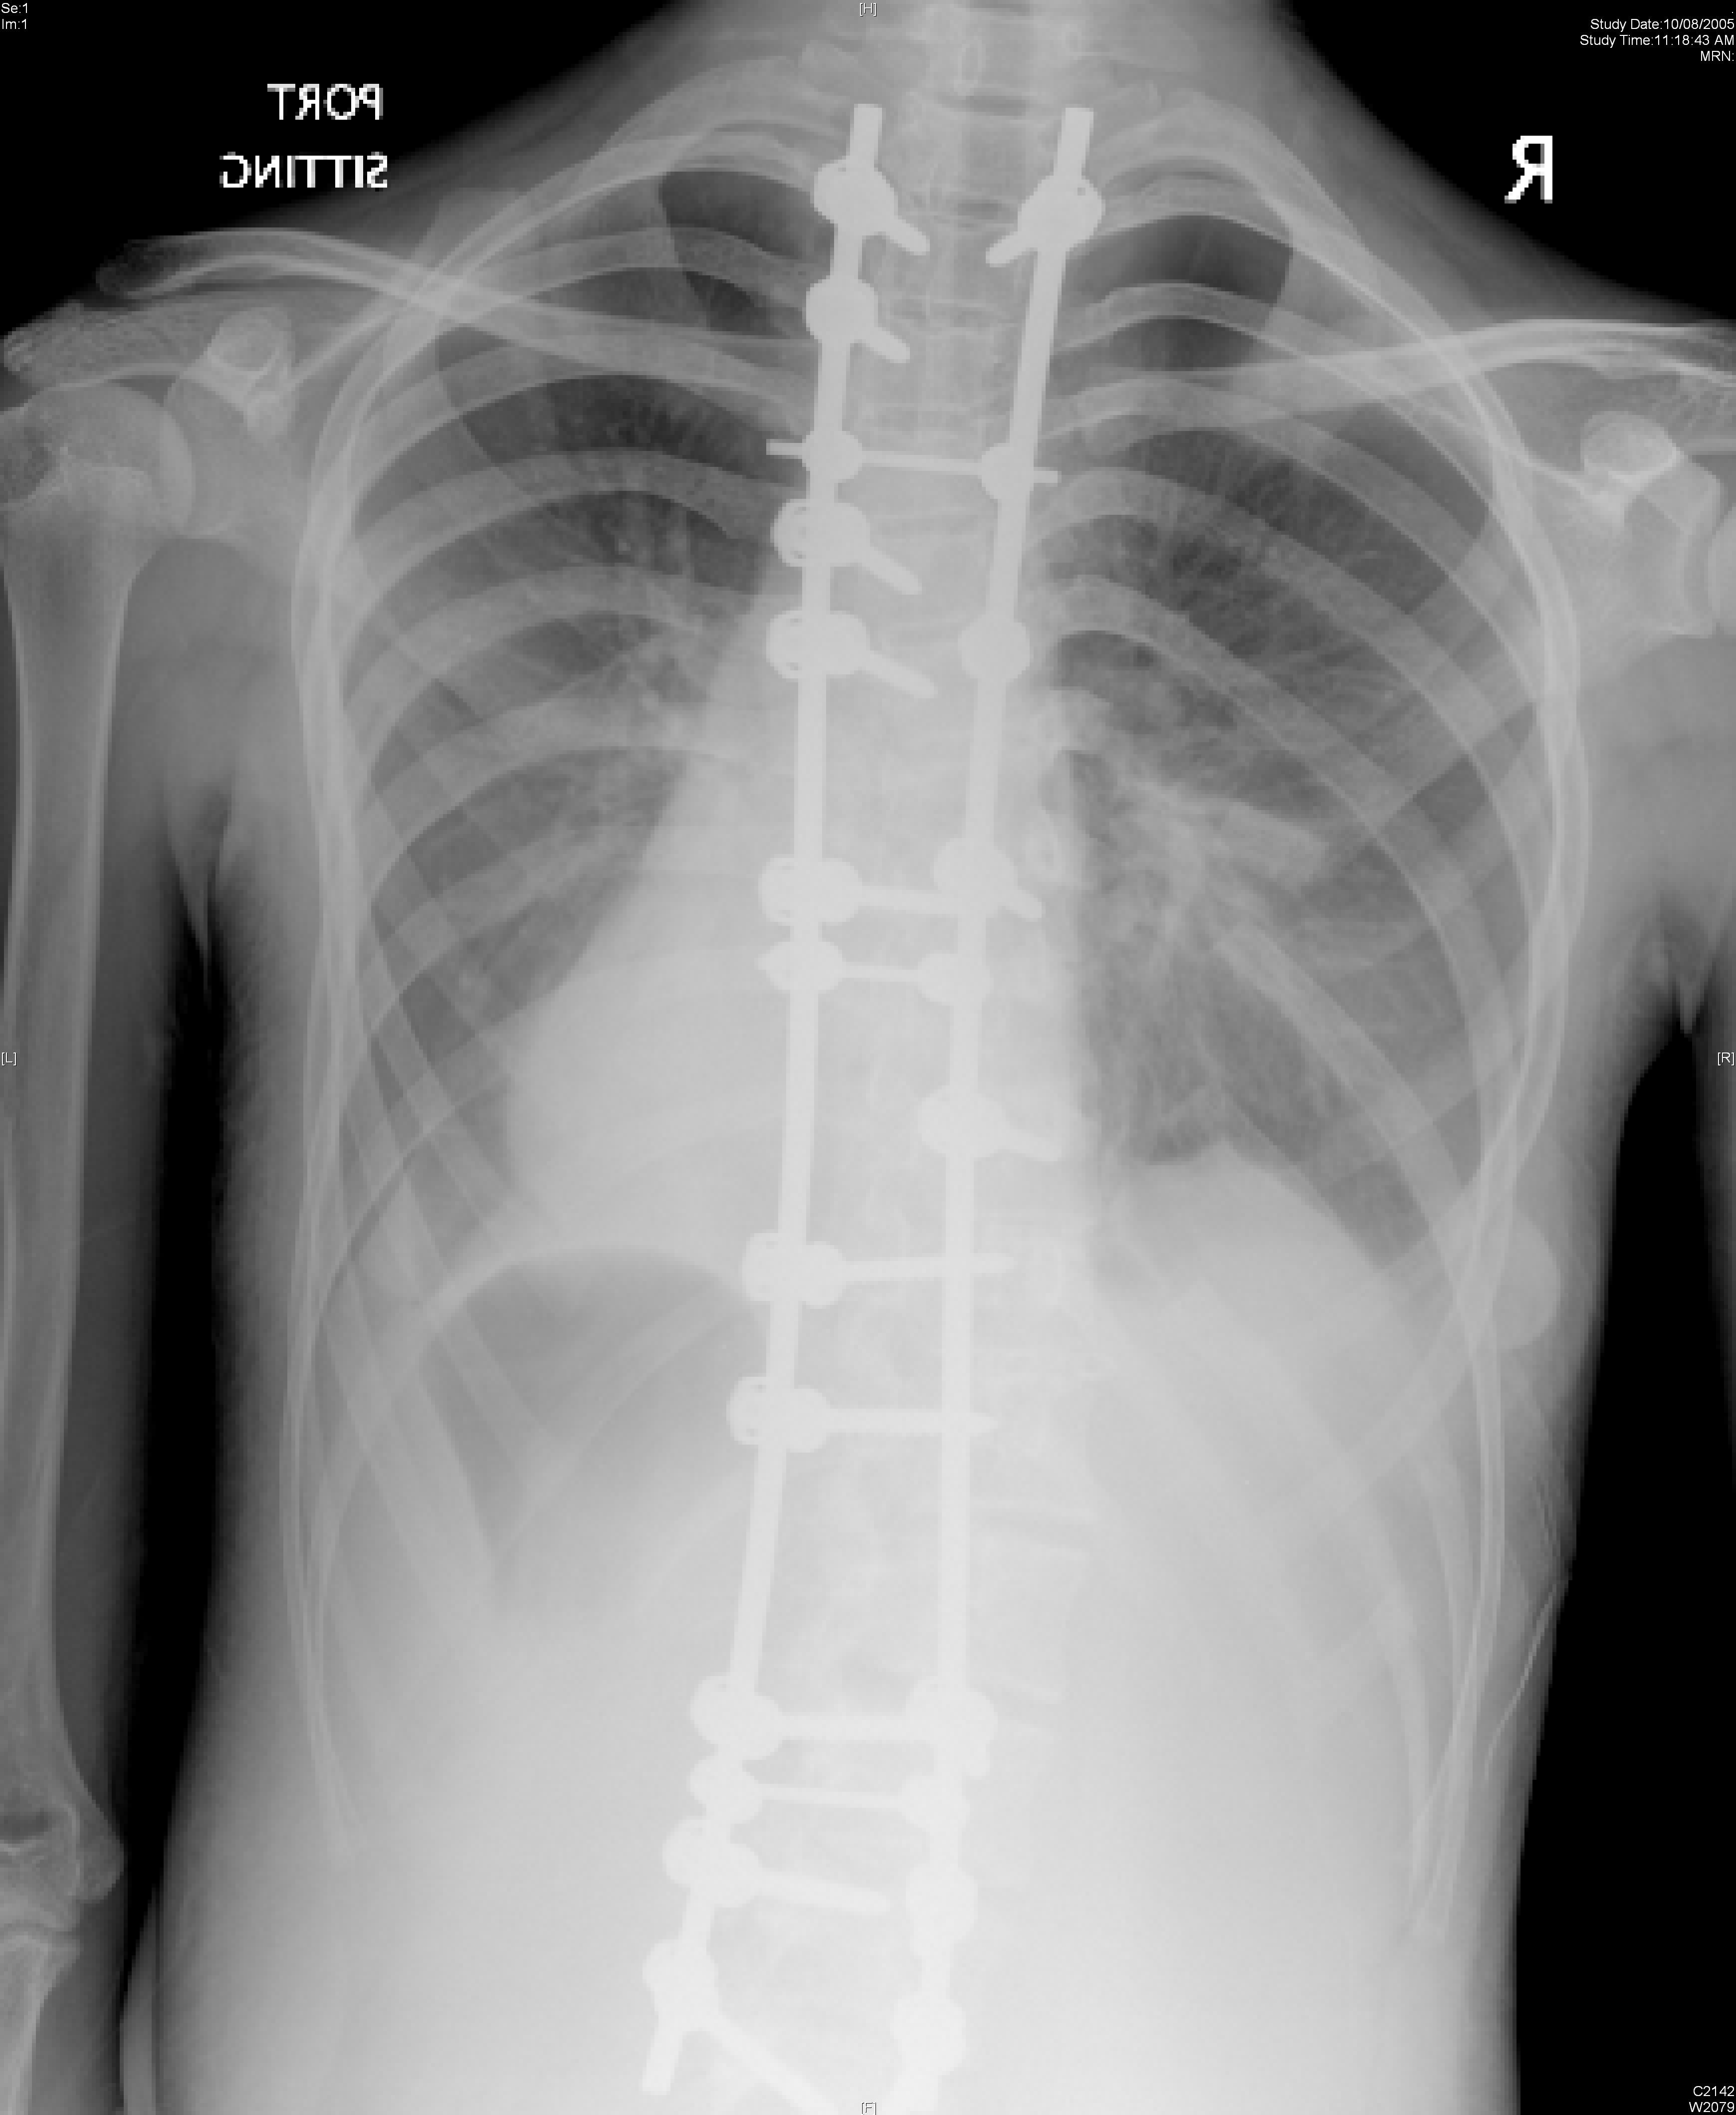

Currently artificial disc replacement can be used for the lumbar or the cervical spine. Many different models have been developed. The majority consists of two metal plates that have teeth to anchor the implant onto the bone of the vertebral bodies. Between the two plates is a metal core or a plastic core made up of polyethylene that allows for motion. Figure 1 shows a lumbar artificial disc replacement. Figure 2 shows a cervical artificial disc replacement.

The technique to insert an artificial disc (whether in the neck or low back) is routine and safe. For the cervical spine it involves going from the front of the neck. For the lumbar spine, it involves going through the abdomen. The procedure begins by removing the gelatinous disc between the vertebrae. Once the disc is removed, two metal plates are pressed into the bony endplates above and below the space now vacated by the disc. Metal spikes hold these plates in place on the bone. Eventually bone will grow over and around the metal plates. In between the metal plates is a metal or plastic core made of a polyethylene. Figure 3 shows the artificial disc placed in the spine.